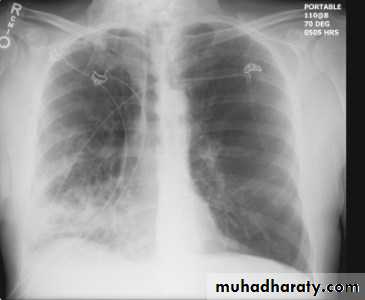

Hydropneumothorax is a term given to the concurrent presence of a pneumothorax as well as a hydrothorax (i.e. air and fluid) in the pleural space.Plain radiographs

On an erect chest radiograph, recognition of hydropneumothorax can be rather easy - and is clasically shown as an air-fluid level. On the supine radiograph, this may be more challenging where a sharp pleural line is bordered by increased opacity lateral to it within the pleural space may sometimes suggest towards the diagnosis 3,